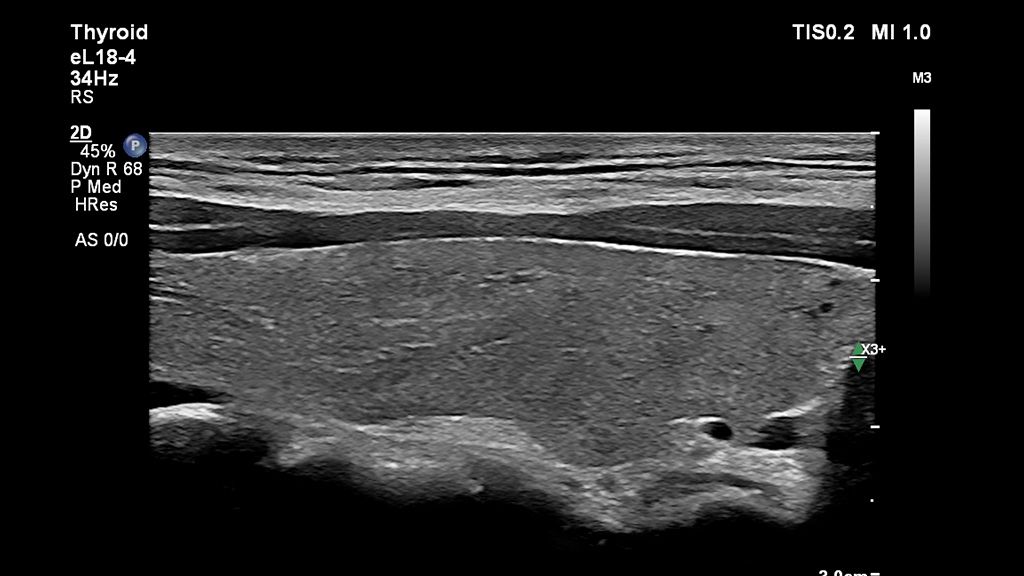

Dr Andrew McQueen of Freeman Hospital shares his experience working with the mL26-8 and eL18-4 ultra high-frequency linear transducers for neck ultrasound.

If we can increase our confidence in the subtle diagnosis at the time of scanning, we can triage the subsequent investigation pathway appropriately and prevent delayed diagnoses.